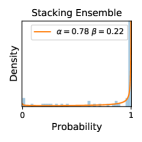

5.1 Distribution of Uncertainty Scores

Distribution of Uncertainty Scores Across Different Severity Levels As explained in Section 3, each uncertainty metric essentially defines an order/ranking among the data points. We conducted an analysis to better understand what data will be assigned high uncertainty under a particular uncertainty metric . Picking out the highest ranked data points (), we calculated the ratio of data points from each SL. Figure 4 summarizes the results as box plots for the Kaggle-DR and the Messidor-2 datasets; additional detailed statistics can be found in Table S.1 in the supplementary materials. From the plot and table, SL1 & SL2 examples account for a higher proportion among the top-ranked uncertain examples across the three ensemble methods. This finding matches our intuition that incipient disease examples (SL1 & SL2) are more likely to be considered uncertain by ensemble methods due to their ambiguity.

False Negatives vs. Uncertain Negatives As discussed in Section 2, the FNP measures the probability of the identified uncertain negatives being actual false negatives. The higher the FNP, the more wrong predictions an uncertainty-informed scheme can potentially correct. In Figures 3b, we report the FNP values under different settings from different combinations of ensemble methods and uncertainty metrics. The results in uncertain false negatives and their ratios to the number of uncertain negatives are illustrated in Figures 3a & 3b, respectively. mean gives higher false negative precision values than var, which validates Theorem 1.

Comparing the three ensemble methods in Figure 4, the stacking ensemble method has the highest ratios of SL1 & SL2 data among the high-uncertainty examples it identified under both mean and var. TTA showed slightly better performance than MC-dropout but still falls behind the stacking ensemble method. Considering the fact that SL0 examples accounted for the majority of the dataset, the stacking ensemble method was much more precise (specific) in selecting truly ambiguous data points that were difficult to classify. From Figure 3, we can also see that the stacking ensemble method greatly outperformed the other two methods in finding false negatives under both mean and var uncertainty metrics.

In contrast, the MC-dropout method showed the worst overall performance among the three, as it can be seen from the high ratios of SL0 examples among the uncertain negatives in Figure 4. The histograms in Figure 2 provides another perspective to look into the phenomenon, where a decent proportion of MC-dropout model’s predictions on SL0 inputs entailed low confidence (far from 0 or 1), which from another angle explained why MC-dropout was less specific in terms of lower FNP; many no-DR inputs (i.e. SL0) were erroneously assigned high uncertainty by MC-dropout models.

As discussed in Section 5.1 and Section 5.3 in the main paper, the mean metric and the stacking ensemble will have better performance in the precision (specificity) on the ambiguous data. Here, more detailed results are shown in Figures S.3 & S.6 and Table S.1. Figures S.3 & S.4 show the histograms of the uncertainty score for Kaggle-DR and Messidor-2 datasets that are the in-distribution (i.d.) dataset in our experiment and FigureS.5 & S.6 show the histograms for ImageNet and CIFAR-10 datasets, which is the o.o.d. datasets in our experiment. Each group of histograms contains results from the three evaluated ensemble methods (stacking ensemble, MC-dropout and TTA) and the three uncertainty metrics (mean, var and kl). Additional detailed results not displayed in Figure 4 can be found in Table S.1, which shows the proportion of the data of different SLs varies across different . For comparison, we also included in Table S.1 the results from single learners, and the proportions of data of different SLs (before any selection was made).